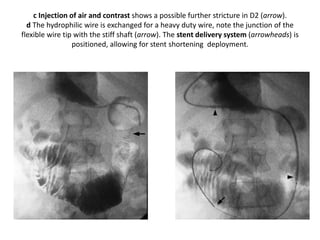

Infiltrative gastric carcinoma producing

a linitis plastica or “leather bottle appearance”

Scirrhous gastric carcinoma. Gastroscopy

revealed irregular

mucosal folds in the body of the stomach (a).

Biopsies were negative

and follow-up examinations with a barium

meal (b) and ultrasound (c)